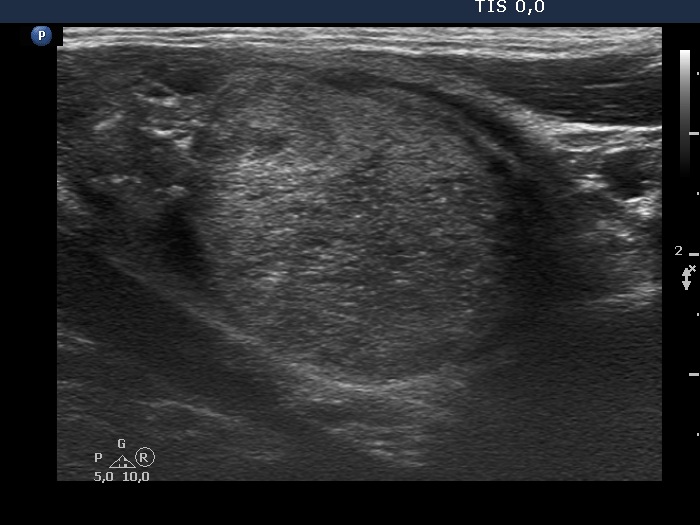

The echogenicity of the nodule - case 2159 (ultrasonographic picture 6)

Left lobe, another longitudinal view. The synchronous presence of echogenic lines and granules is the evidence of connective tissue.